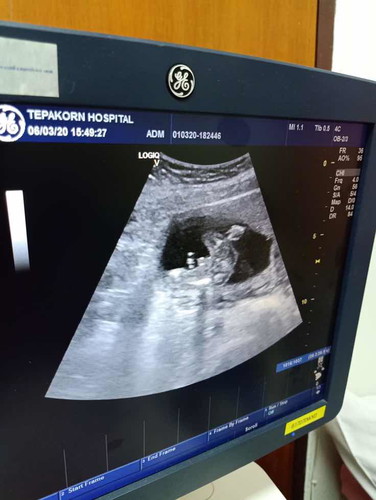

รบกวนถามแม่ๆหน่อยค่ะ ผู้หญิง หรือ ผู้ชายค่ะ หมอบอกว่าผู้ชายค่ะ แต่ไม่ชัวร์เท่าไรค่ะ

น่าจะผู้ชายค่ะ มียื่นๆออกมา

เชื่อตามหมอเลยคะ